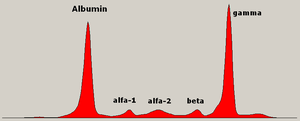

يُشخص المرض مخبريا بعمل عدة فحوصات و تشمل الفحوصات الوظيفية للكلية و قياس كمية الكالسيوم في الدم و عد مكونات الدم. و يستخدم الترحيل الكهربائي للبروتينات للتحري عن بعض البروتينات الغير طبيعية التي يتم إنتاجها بواسطة الخلايا السرطانية. للتحري عن أية كسور في العظام يتم تصوير المريض إشعاعيا بواسطة الجهاز الطبقي أو جهاز الرنين المغناطيسي.

فحوص الدم